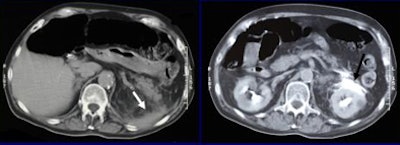

| A 52-year-old man after a motor vehicle collision. Initial axial CT scan (left) shows free fluid (arrow). This finding was suspicious for pancreatic injury. Five-minute delayed scan (right) demonstrates rupture of the upper pole of the left kidney associated with contrast material extravasation (arrow). The patient was treated conservatively. |